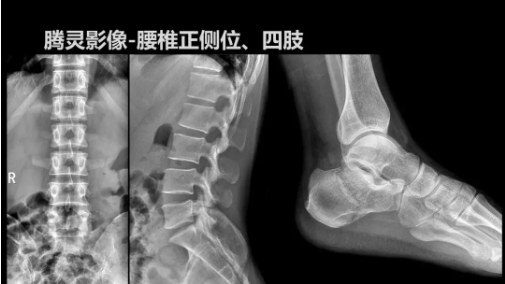

“騰靈”是安健科技的第四代動態(tài)DR產(chǎn)品,可實現(xiàn)全科室應(yīng)用。如各類常規(guī)的X線檢查、消化道檢查、骨科檢查、婦科、兒科檢查等。此外,安健科技為“騰靈”在真正意義上實現(xiàn)多科室、多功能診斷進行了多項針對性設(shè)計。